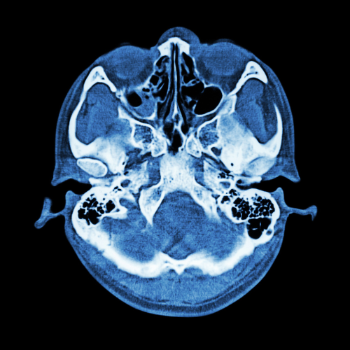

The skull base is a critical area housing several vital structures, including the brain, nerves, and blood vessels. Conditions affecting this region, such as tumors, vascular disorders, and congenital anomalies, can lead to debilitating symptoms and significantly impact an individual's quality of life. For Indian patients like Rajesh, the emotional toll can be as daunting as the physical challenges. The fear of losing independence, the anxiety of an uncertain future, and the burden on loved ones can be overwhelming.

Skull base surgery offers a beacon of hope for patients grappling with such conditions. It is a sophisticated surgical procedure that requires a multidisciplinary approach, often involving neurosurgeons, ENT specialists, and other experts working in tandem. This surgery is not merely about removing a tumor or correcting a malformation; it's about restoring hope, alleviating fear, and reclaiming life.

Rajesh, after extensive consultations and research, decided to undergo skull base surgery at a renowned medical facility in India. The decision was not easy, but the potential benefits far outweighed the risks. The surgery aimed to remove a benign tumor pressing against his optic nerve, which was responsible for his vision problems and headaches. The procedure, though complex, promised a significant improvement in Rajesh's symptoms and overall well-being.